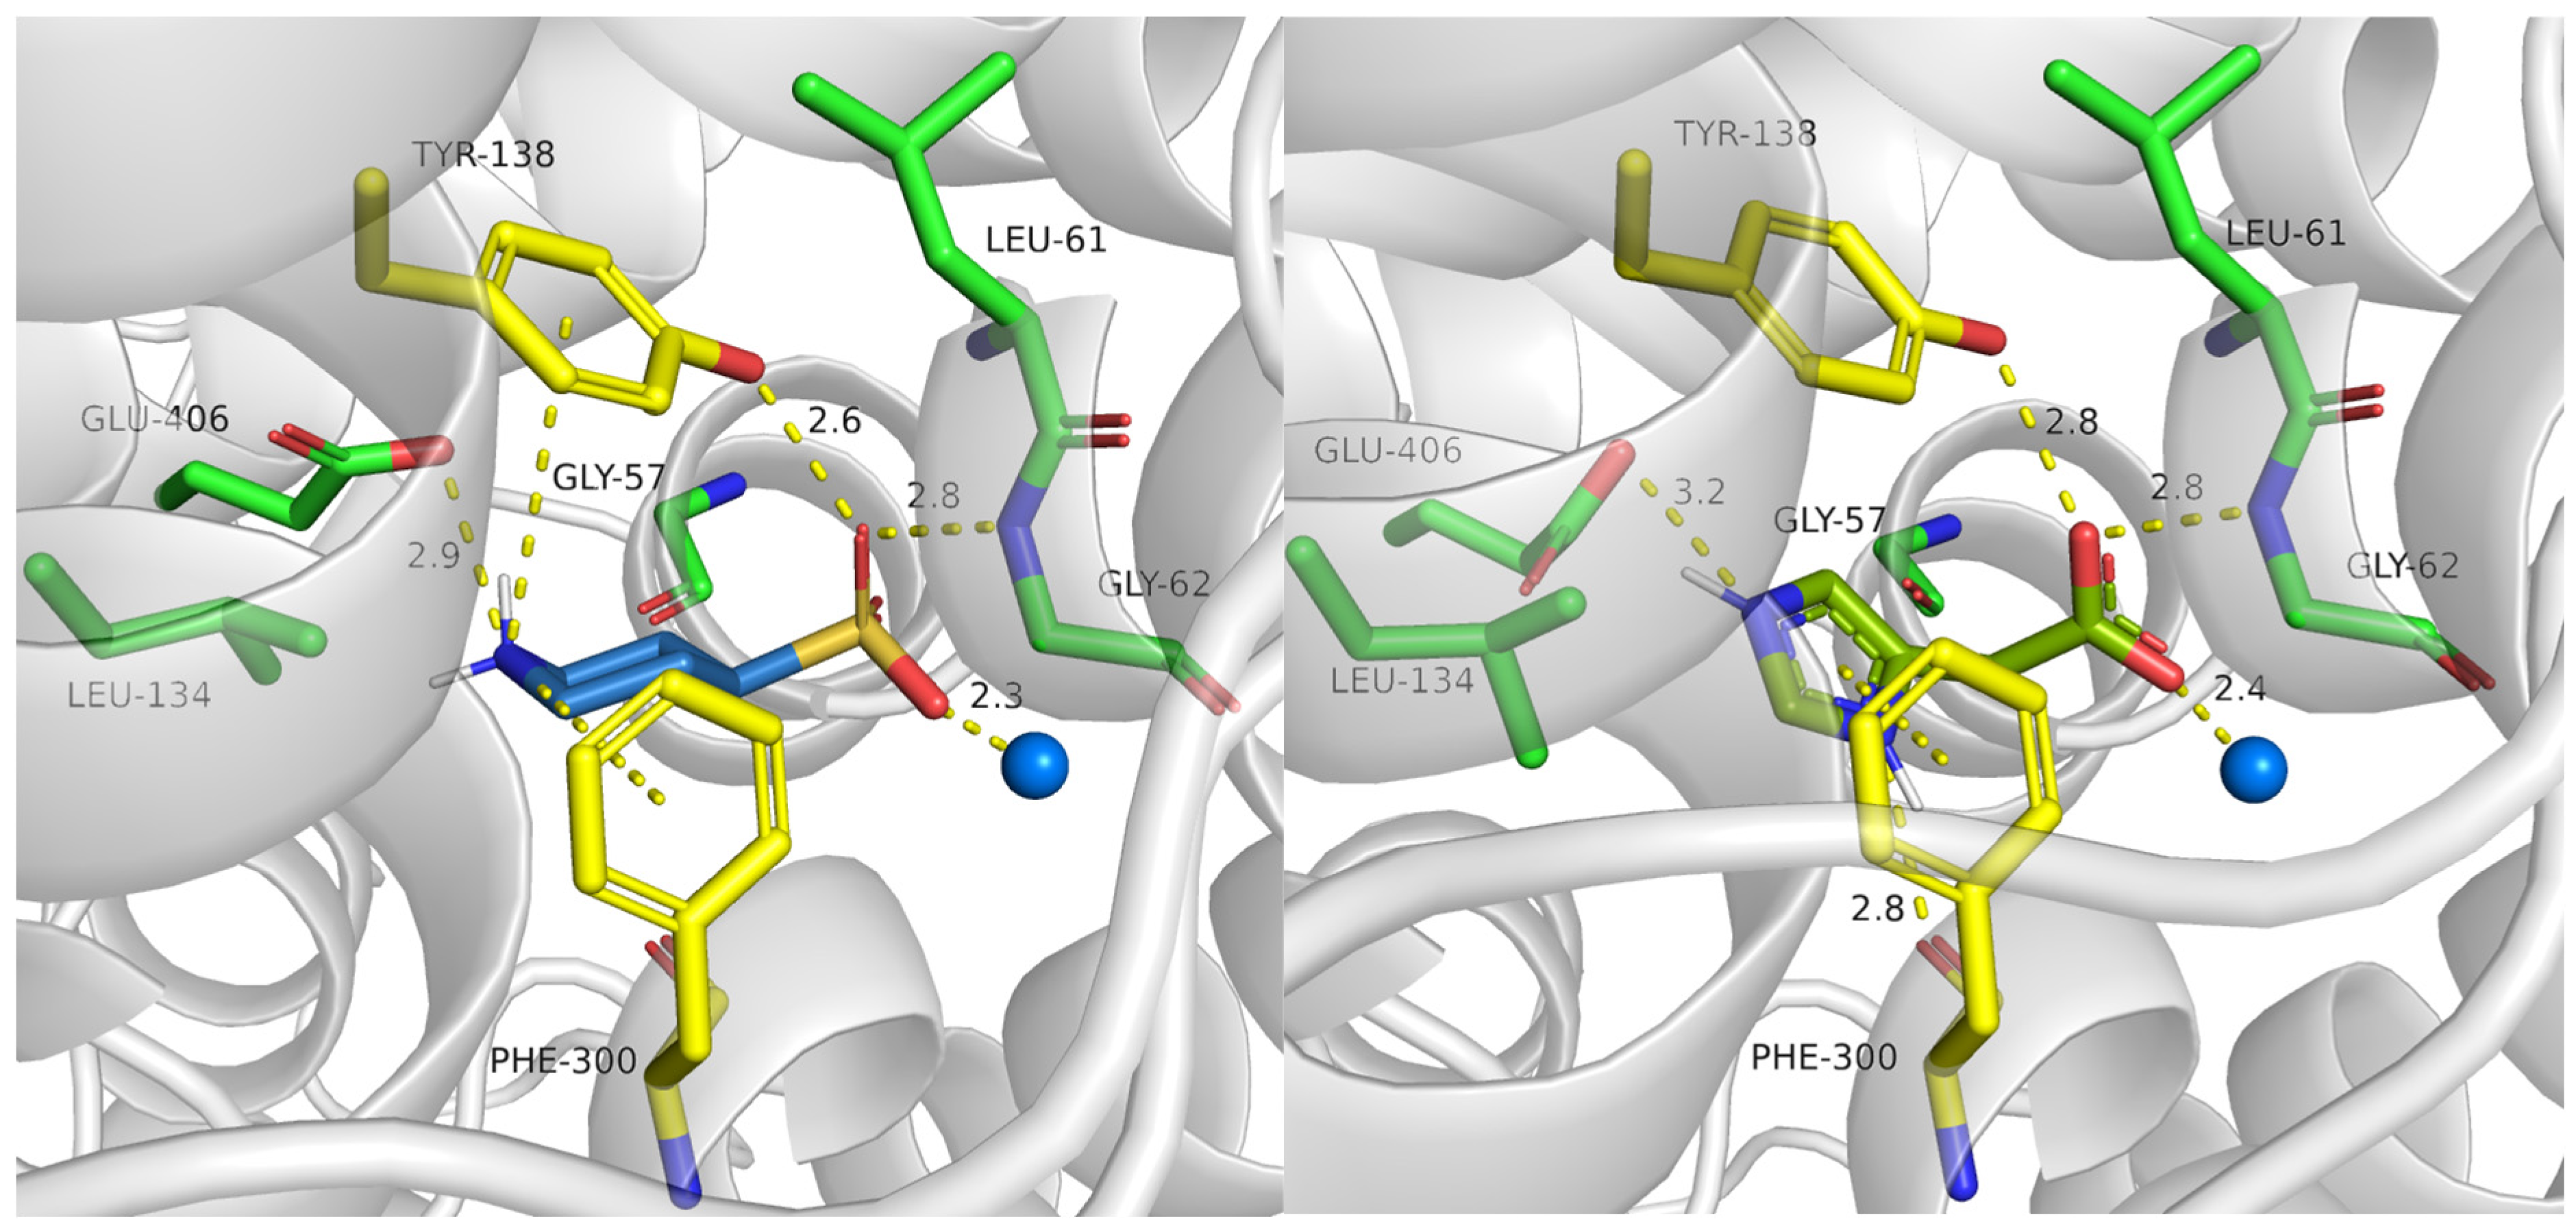

2.3.1. TauT Ligands Binding Mode

2.3.2. Binding of Taurine Transporter Inhibitors

2.4. Role of Mutations in Taurine Transporter

2.4.1. Glu406 Is Crucial for SLC6A6 Transporter Activity

2.4.2. Importance of Gly57 and Leu306 for SLC6A6 Activity